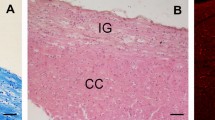

Periventricular pathway (PVP) system of the developing human cerebrum is situated medial to the intermediate zone in the close proximity to proliferative cell compartments. In order to elucidate chemical properties and developing trajectories of the PVP we used DTI in combination with acetylcholinesterase histochemistry, SNAP-25 immunocytochemistry and axonal cytoskeletal markers (SMI312, MAP1b) immunocytochemistry on postmortem paraformaldehyde-fixed brains of 30 human fetuses ranging in age from 10 to 38 postconceptional weeks (PCW), 2 infants (age 1–3 months) and 1 adult brain. The PVP appears in the early fetal period (10–13 PCW) as two defined fibre bundles: the corpus callosum (CC) and the fetal fronto-occipital fascicle (FOF). In the midfetal period (15–18 PCW), all four components of the PVP can be identified: (1) the CC, which at rostral levels forms a voluminous callosal plate; (2) the FOF, with SNAP-25-positive fibers; (3) the fronto-pontine pathway (FPP) which for a short distance runs within the PVP; and (4) the subcallosal fascicle of Muratoff (SFM) which contains cortico-caudate projections. The PVPs are situated medial to the internal capsule at the level of the cortico-striatal junction; they remain prominent during the late fetal and early preterm period (19–28 PCW) and represent a portion of the wider periventricular crossroad of growing associative, callosal and projection pathways. In the perinatal period, the PVPs change their topographical relationships, decrease in size and the FOF looses its SNAP-25-reactivity. In conclusion, the hitherto undescribed PVP of the human fetal cerebrum contains forerunners of adult associative and projection pathways. Its transient chemical properties and relative exuberance suggest that the PVP may exert influence on the development of cortical connectivity (intermediate targeting) and other neurogenetic events such as neuronal proliferation. The PVP’s topographical position also indicates that it is a major site of vulnerability in hypoxic–ischaemic perinatal brain injury.